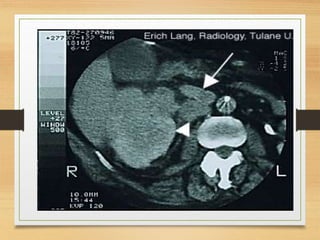

CASE 4

• A 64-year-old man presents with a 2-month history